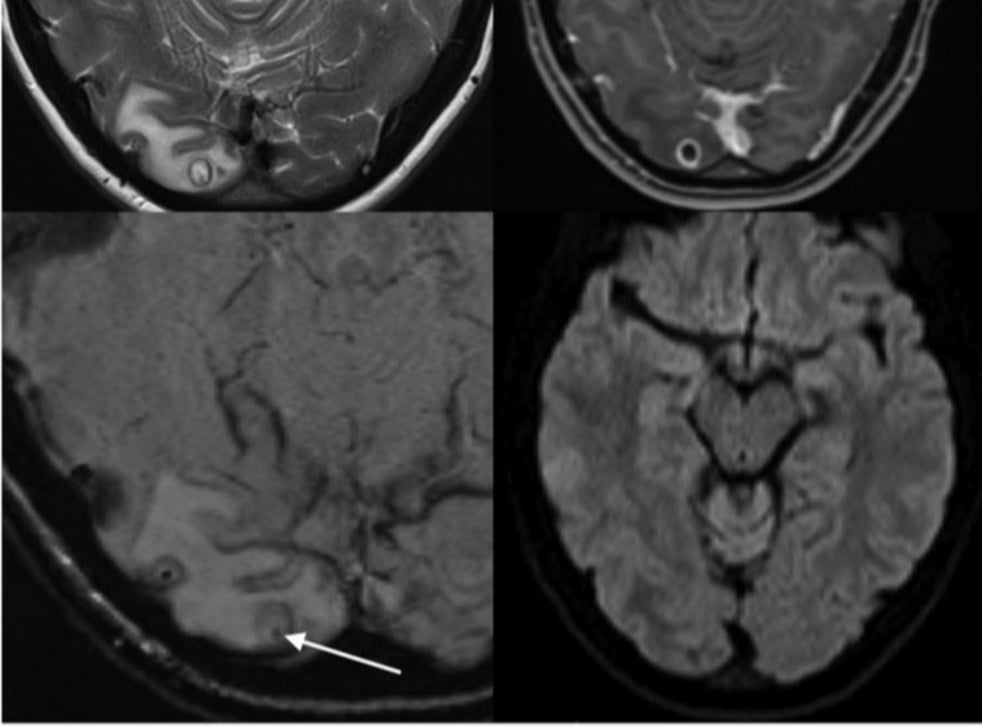

Tapeworm cyst in the brain, MRI scan Stock Photo Alamy Tapeworm In Your Brain [8] the diagnosis can be made by aspiration of a. It has an incredibly complicated life cycle in which individuals get infected by consuming undercooked infected pork. Humans are typically exposed to tapeworms through raw or undercooked food or through food. His brain was infested with tapeworm cysts. people who live with someone with the pork tapeworm have a. Tapeworm In Your Brain.

Tapeworm Cysts In The Brain Photograph by Zephyr/science Photo Library Tapeworm In Your Brain worms wriggling around in your brain — it’s a particularly gruesome image that sounds like it came straight from a b. His brain was infested with tapeworm cysts. the most common one is taenia solium, the pork tapeworm. people who live with someone with the pork tapeworm have a greater risk of getting cysticercosis. Inflammation, or swelling,. Tapeworm In Your Brain.